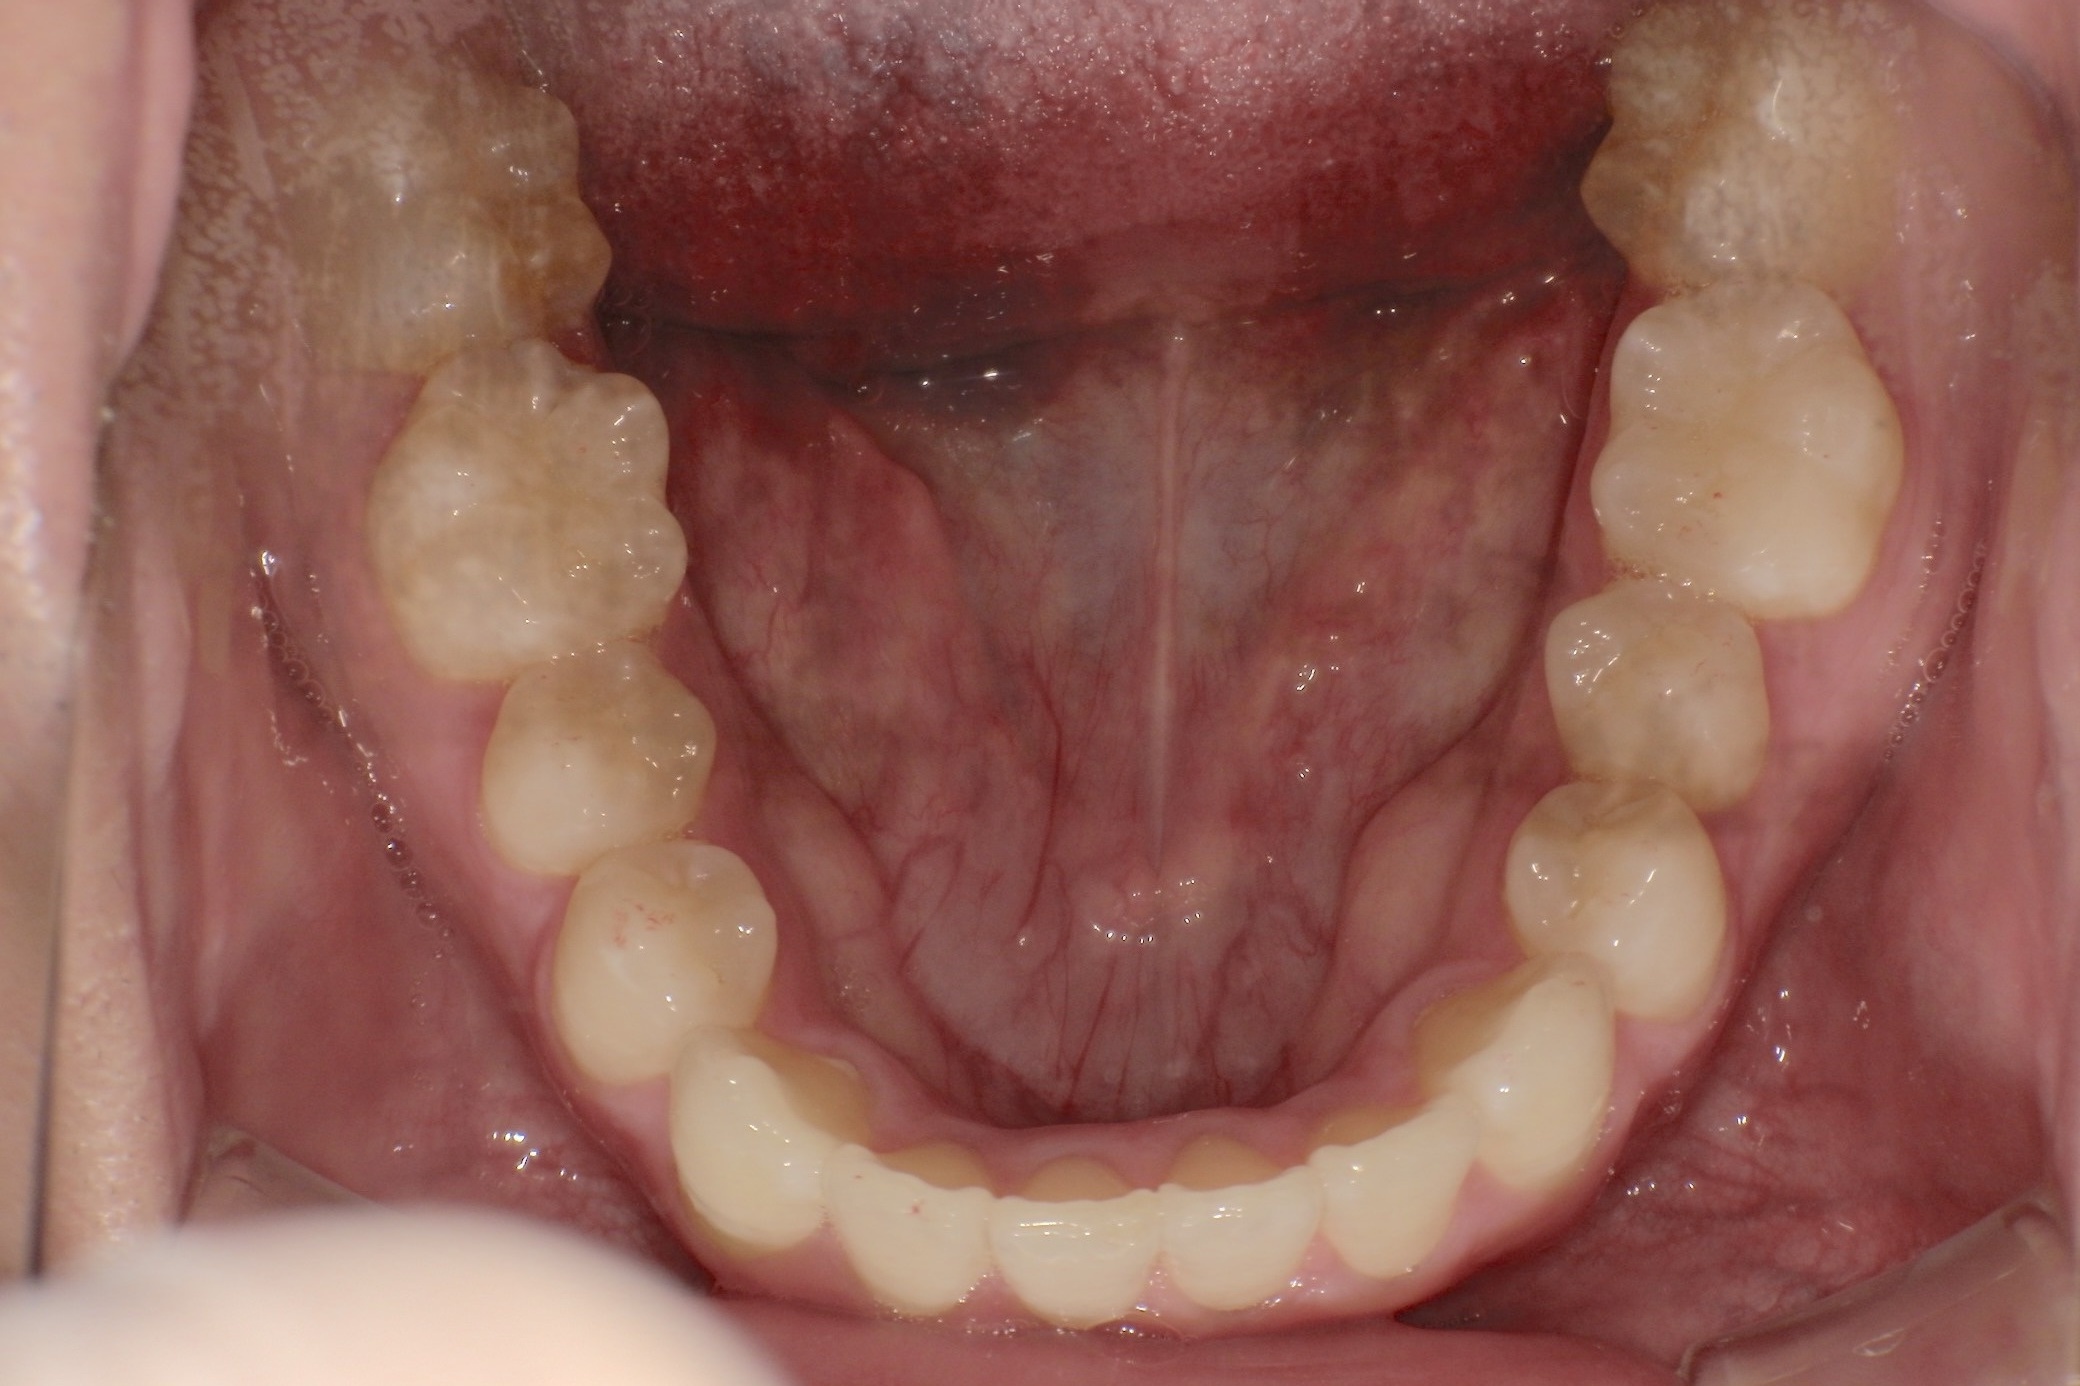

※プライバシー保護のため、実際のご本人ではなくAIによるイメージです

人と接する機会が多く、第一印象を大切にしたいと考え、写真写りや笑顔への自信を高めたいという思いから矯正を決意された矯正当時学生だった22歳男性の H.S.様に、スマイルモア矯正を選んだ理由を伺いました。

| 費用 | 360,000円(税込396,000円) |

| 治療期間 | 11ヶ月 |

| 治療内容 | マウスピースを用いた歯列矯正 |

| 追加処置 | IPR |